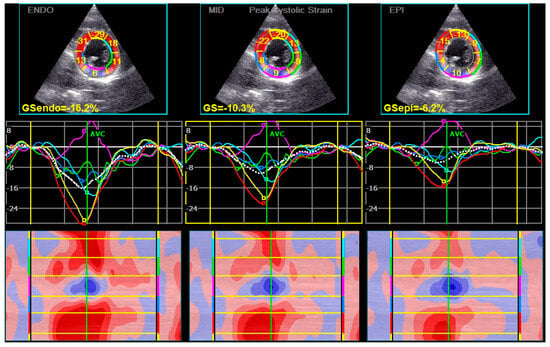

| GLS endo (%) mean ± SD | −21.5 ± 2.9 | −22.5 ± 3.1 | 0.041 |

| GLS mid (%) mean ± SD | −19.1 ± 2.5 | −19.9 ± 2.7 | 0.048 |

| GLS epi (%) mean ± SD | −17.3 ± 2.3 | −17.9 ± 2.4 | 0.064 |

| Peak Systolic LS endo (%) mean ± SD | −20.9 ± 3.1 | −22.0 ± 3.2 | 0.038 |

| Peak Systolic LS mid (%) mean ± SD | −18.6 ± 2.7 | −19.5 ± 2.7 | 0.043 |

| Peak Systolic LS epi (%) mean ± SD | −16.8 ± 2.4 | −17.5 ± 2.5 | 0.056 |